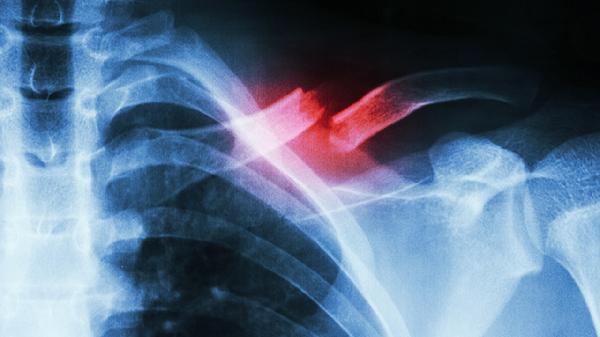

6、发生病理性骨折或变形。

2、患部疼痛,关节与肢体有局部肿块及肿胀。

3、患部之关节与肢体运动受限制。